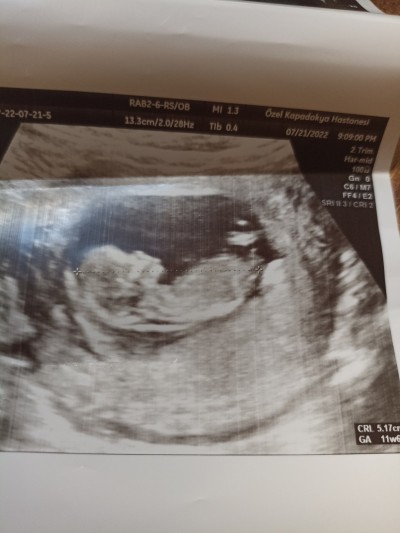

Arkadaşlar merhaba bugün

12 haftalık olduk doktor cinsiyeti söylemedi sizce nedir cevaplarsanız sevinirim teşekkürler

Gebelik haftası 12